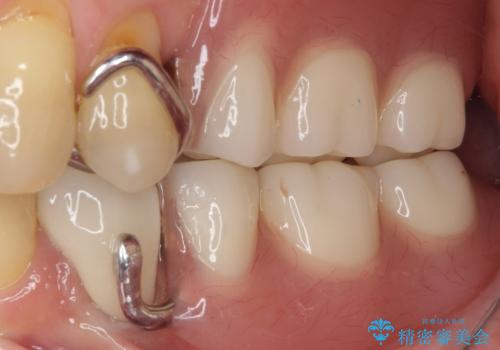

自費治療の義歯は装着感がとても良いですが、急に入れ歯を装着すると、異物感が強く継続使用できなくなるため、仮歯の期間中に保険治療での義歯を装着してもらい、口腔内を義歯に慣れさせるようにしました。

より適合の良い義歯とするため、セラミッククラウンなどは義歯の設計に合わせた土台の歯となるよう全て再製作をし、安定感に優れた義歯を製作することができました。